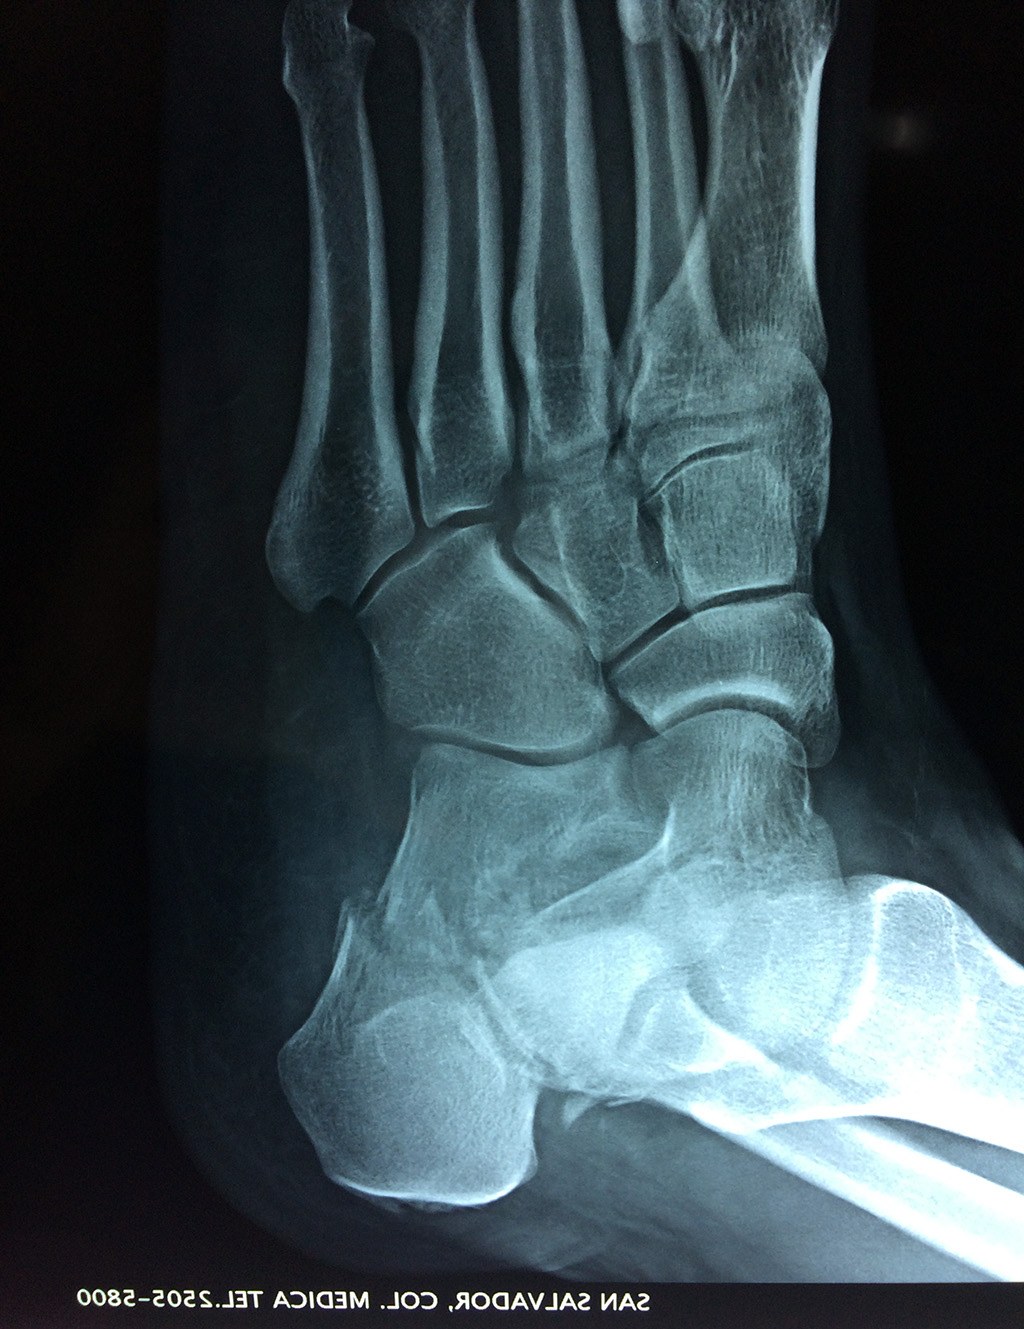

En su cara posterior recibe la inserción del tendón más plantar, implicada en diversas enfermedades como la fascitis o el espolón calcáneo. La posición del calcáneo en relación al astrágalo (articulación subastragalina) y al suelo determinan la posición de retropié en varo, en valgo o neutra.

Los retropiés varos y sobre todo, los retropiés valgos, son responsables de distintas enfermedades del aparato locomotor y contribuyen a que aparezcan alteraciones de la marcha normal fisiológica, con consecuencias clínicas importantes (dolor, sobrecargas, aplanamiento, fatiga muscular, juanetes, etc.) tanto a nivel de pie como a nivel del miembro inferior.

De todo esto se deriva que su posicionamiento espacial es muy importante para contribuir a una marcha correcta y a la salud del resto del conjunto articular del pie.